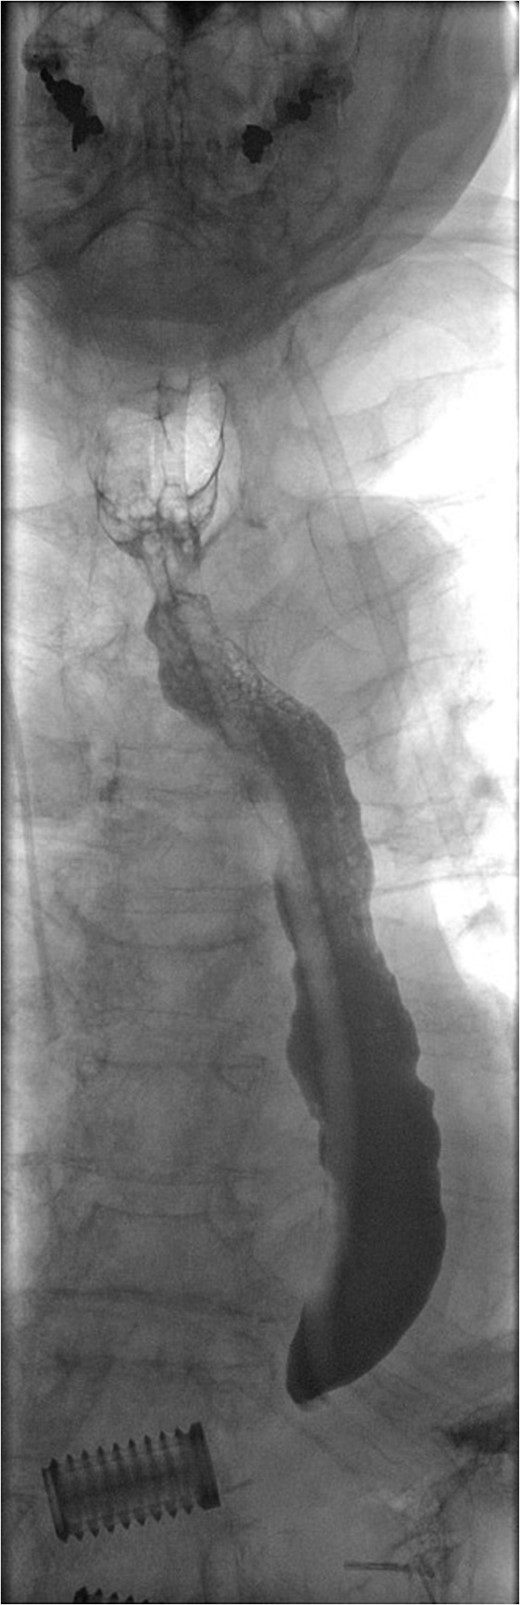

For management of this oesophageal perforation and definitive management of her gastric perforation, the patient was referred to the authors’ unit, a tertiary referral centre for upper GI surgery. In the first instance, a water-soluble contrast swallow was performed to assess the status of the oesophageal perforation. This demonstrated no leak of contrast (Fig. 3) and therefore a diagnostic endoscopy under general anaesthesia was performed in order to assess the cervical oesophagus and also the known gastric perforation. This endoscopy demonstrated a healed oesophageal perforation but persistent gastric perforation with established cavity (Fig. 4) containing an existing transabdominal Robinson drain. The cavity was felt to be of a size likely to heal without the need for further negative pressure vacuum therapy, so a T-tube was placed across it. The established track of the existing abdominal drain was used to guide placement of the T-tube. A nasojejunal feeding tube was placed under vision.

Water-soluble contrast swallow study demonstrating free flow of contrast from oropharynx to stomach with no evidence of leak.